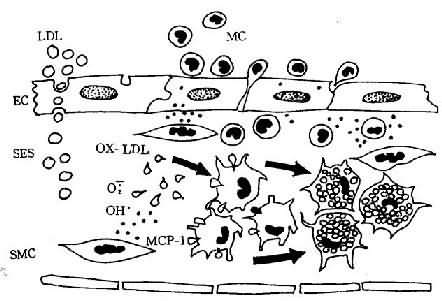

OX-LDL、OX-Lp(a)可与巨噬细胞表面的清道夫受体结合而被摄取。这些受体对胆固醇无下调作用,因而被巨噬细胞摄取的脂质愈来愈多,直至形成泡沫细胞(foam cell)(图8-1)。

图8-1 单核细胞迁入内膜及泡沫细胞形成模式图

LDL渗入内皮下间隙(SES),被氧自由基氧化修饰;MCP-1释放,单核细胞(MC)迁入内膜,OX-LDL与巨噬细胞表面的清道夫受体结合而被摄取,泡沫细胞形成(EC:内皮细胞,SMC:平滑肌细胞)(仿Schwartz)